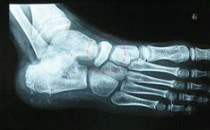

跟骨

例子

病症描述:AS在青春期前发病可能会踝关节和脚部关节肿痛,出现跟骨骨刺。